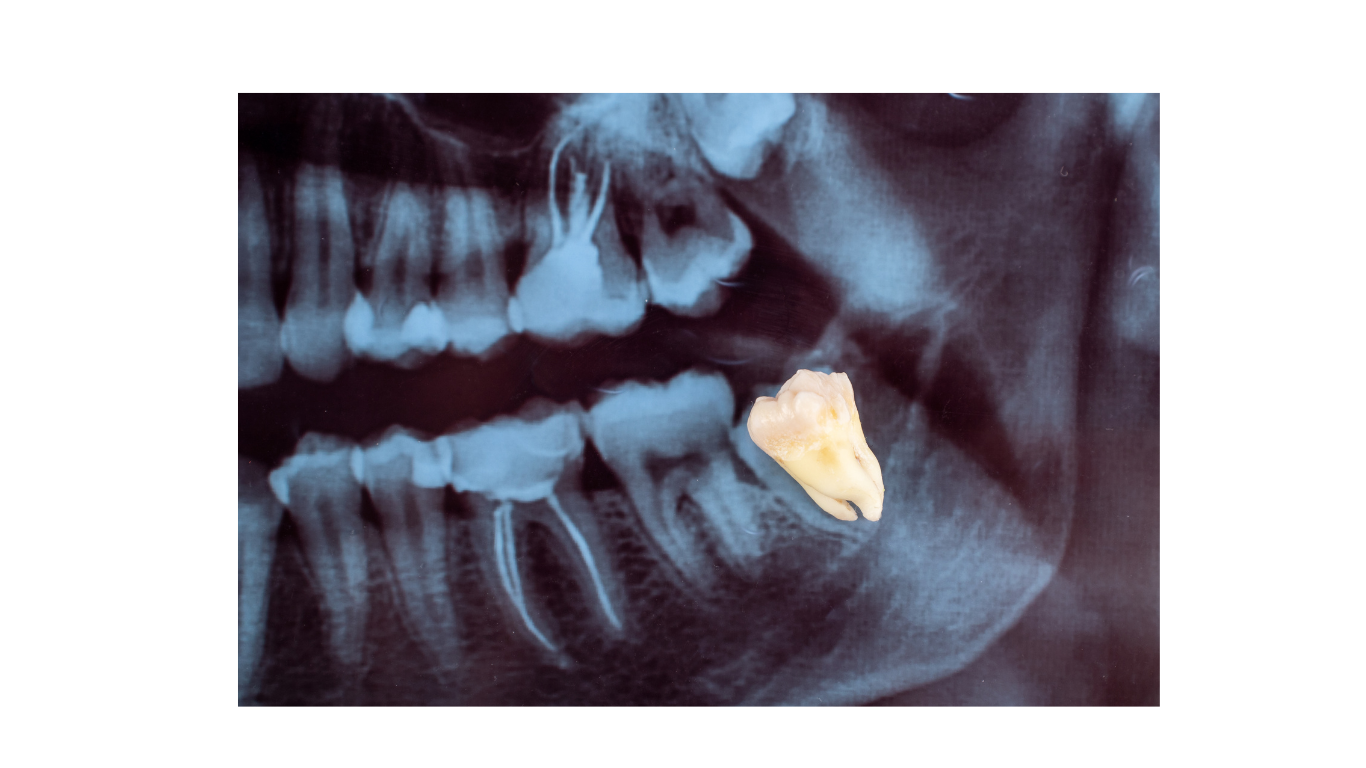

Wisdom Teeth Extractions

Wisdom teeth are the third set of molars that typically emerge in your late teens or early twenties. For many people, these teeth can cause problems if there isn’t enough space in the mouth, or if they grow in at an angle and become impacted.

Wisdom tooth extractions can range from a routine extraction to a surgical one, depending on whether the teeth are impacted or fully erupted. We’ll use X-rays to assess the position of your wisdom teeth and create a treatment plan tailored to your needs. After numbing the area or using sedation, we’ll remove the teeth and provide aftercare instructions to help you heal quickly and comfortably.